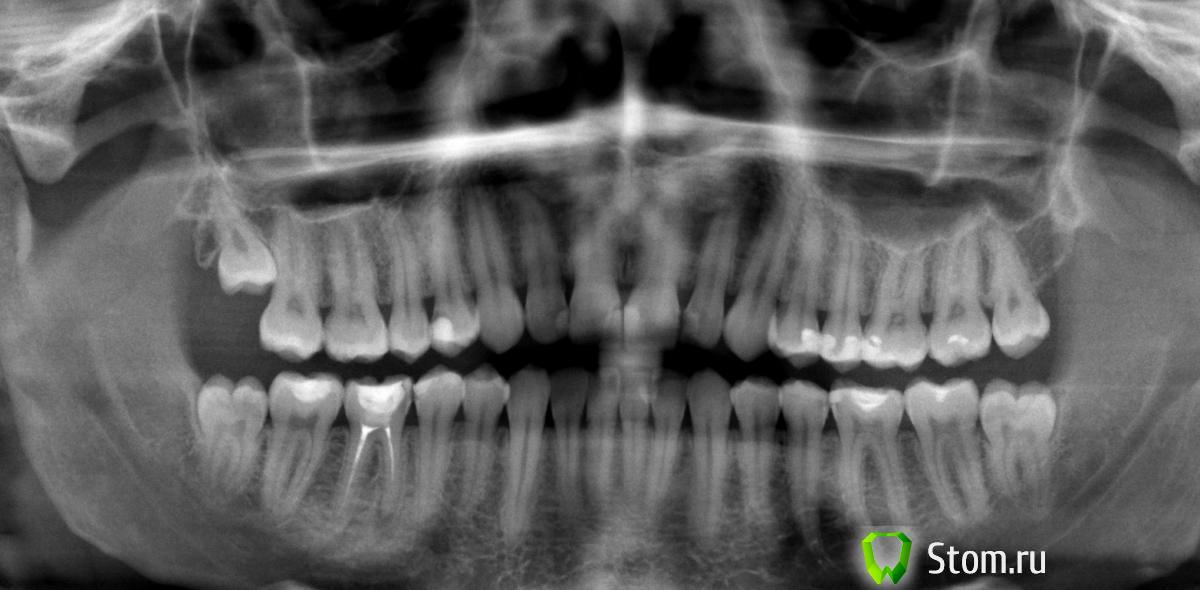

Pekarnik Опубликовано 23 января, 2012 Поделиться Опубликовано 23 января, 2012 Здравствуйте. Мужчина. 26 лет. Москва. Заранее извиняюсь за кривые объяснения и большое количество текста с грамматическими ошибками. -В 2004 году Доктор А удалил нервы, почистили каналы, делал снимки и запломбировали 46 зуб в платном стоматологическом отделении одной Гос Клиники. -В 2005 году показался тому же Доктору А, т.к. иногда возникали неприятные ощущения в области 46-ки. Доктор А после осмотра (не помню дедали ли снимок)сказал, что вероятнее всего это просто повышенная чувствительность в соседнем 45-ом зубе и предложил пока ничего не трогать и понаблюдать.-Всё нормализовалось. Прошло несколько лет.- В 2009 году сделали СНИМОК-1. Обнаружили гранулему на данном зубе, но я ничего стать делать - осел.В общем только сейчас добрался до доктора. Тот же Доктор А. Сделали Снимок-2.- Доктор А теперь говорит, что лечить гранулему в данном случае нецелесообразно ввиду плохого состояния зуба (большая пломба на 2 стенках, ослабленный зуб и корень) и что в процессе лечения гранулемы и каналов - есть большая вероятность что зуб, вернее корень сломается. Доктор А предлагает не лечить сейчас каналы и гранулему, а пока просто понаблюдать, делая снимок раз в пол года и настраиваться, что потом сразу удаление и имплант. Говорит, что гранулема не очень большая и что если нет жалоб - то можно не спешить, что она ещё может и 5 и 7 лет быть в таком "сонном состоянии" состоянии.Учитывая вышесказанное лечить у Доктора А зуб на котором возникла гранулема после его же лечения я не стал. Сходил ещё к 2 докторам. -В одной маленькой частной клинике Доктор Б предлагают перелечить каналы за 15 000 + коронка от 15000. + говорят что возможно рассасывается не кость у верхушки корня, а возможно и сам корень!!! Это видно на снимке?-В одной средней сетевой клинике Доктор В предлагает не перелечивать зуб а поставить пломбу и наблюдать раз в пол года.Ещё стоит упомянуть, что у зуба появился красноватый оттенок, врач сказал что заделан резорцин-формалином скорее всего.---------------------------------------------------------------------------------------- Прикладываю два снимка 2009 и декабрь 2011 года.------------------------------------------------------------------------- вопросы:1. Что делать с зубом? Не трогать (советуют 2 доктора)и поставить пломбу, так как : а. Особо не беспокоит и вроде как не увеличивается с 2004 года. б. Есть вероятность что не смогут распломбировать формалин и пройти каналы. в. Только потревожат гранулему, усугубится ситуация. г. Лечение относительно дорогое. Перелечивать каналы. Долбить формалин и ставит коронку, так как: а. гранулема может вырасти значительно за несколько месяцев и не удастся её контролировать даже делая снимки раз в пол года. б. пломба скоро сломается, зуб разрушится дальше и будет сложно поставить потом коронку. 2. Если перелечивать, то насколько это сложно учитывая резорциновые каналы. Нужна ли специальная квалификация, опыт, микроскоп, или это стандартная процедура в настоящее время и любой среднестатистический терапевт это выполняет на ура? Смущает, что доктор В (стаж более 5 лет), который в целом меня устраивает - настойчиво рекомендует не ковырять зуб, а ставить пломбу. Может это быть обусловлено в том числе не желанием сложной работы или недостатком квалификации, неуверенность за результат? 3. Можно ли и стоит ли данный случай (возникновение гранулемы) считать некачественным лечением и просить провести бесплатное лечение в отделении доктора А, который лечил эти каналы? Большое спасибо! Ссылка на комментарий